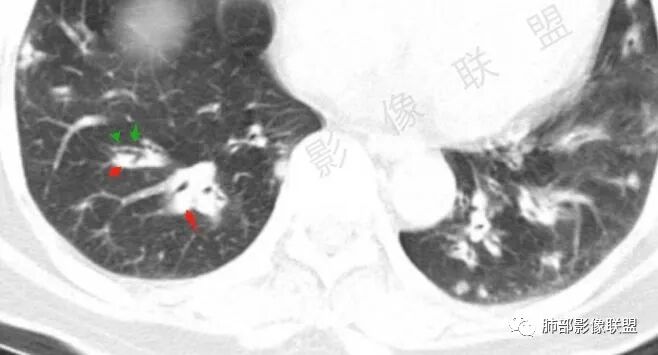

胸CT:双中下肺支气管壁明显增厚,双下肺胸膜下可见实变区。部分病变呈楔形影。

双肺多发大小不等结节,周围伴有晕征,边界模糊,部分结节内似可见支气管影,双肺血管束明显比支气管增粗,临床有感染症状,考虑GPA,疱疹病毒。

影像上:多发结节沿血管分布;双下叶支气管血管束简直增厚,偏血管,支气管通畅

首先肺部气道来源的病变不符合

因为支气管壁增厚,远端应该小气道病变,这个不是,反而是血管增粗明显

加上结节的分布,支持血管相关病变

两肺多发结片影,这个病灶很小,但是中间可见支气管影,支气管炎一般不会包在支气管周围,支气管周围间质可能大,包括血管,淋巴等。一般支气管这样穿行的,被包绕的,血管炎,淋巴瘤等这种间质起源比较多见